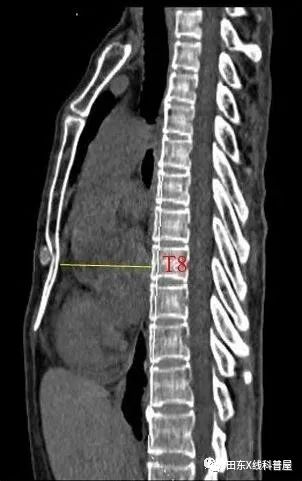

胸椎曲度弧高(左侧位胸片测量):T4-T12做一连线,测T8椎体前缘与该直线的垂直距离,其距离若<12mm,可考虑SBS。

测量胸廓前后径/横径比值≤0.33。

具体出来:胸椎曲度孤高<12mm,胸廓前后径/横径比值≤0.33。